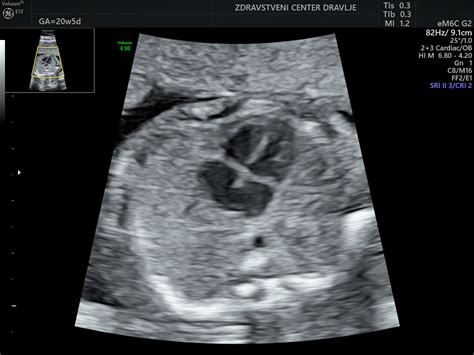

Ultrazvok v tem tednu omogoča oceno različnih parametrov, ki so pomembni za spremljanje zdravja ploda. Dihalne gibe ocenjujemo v vzdolžnem ali prečnem položaju, pri čemer opazujemo gibanje trebušne prepone. Če dihalni gibi trajajo 60 sekund v 30 minutah, plod dobi 2 točki; če trajajo 30-60 sekund, 1 točko; če pa trajajo manj kot 30 sekund ali jih ni, dobi 0 točk. Prve dihalne gibe plod začne izvajati že v prvem trimesečju.

Pri fetalnem biofizikalnem profilu ocenjujemo tudi količino plodovnice z merjenjem najglobjega navpičnega žepa tekočine. Če je ta žep globlji od 2 cm, plod dobi 2 točki; če je globok 1-2 cm, 1 točko; če pa je globok manj kot 1 cm, 0 točk. O oligohidramniju govorimo, če je v žepu manj kot 2 cm plodovnice, o polihidramnionu pa, če je žep večji od 12 cm. Normalna količina plodovnice je, če je najgloblji žep dolg od 3-8 cm. Indeks plodovnice (AFI) je seštevek najglobljih žepov v štirih kvadrantih maternice.

Ocena zrelosti posteljice je prav tako pomembna. Poznamo štiri stopnje zrelosti (0, I, II, III), ki kažejo na njeno staranje. Na sliki vidimo posteljico 0. stopnje zrelosti, kjer je horionska plošča ravna, posteljica homogena brez ehogenih struktur, bazalna plošča pa prav tako brez ehogenih struktur.

Merjenje pretokov v popkovnični arteriji s pomočjo barvnega in pulzirajočega Dopplerja je še ena pomembna ultrazvočna metoda. Izmeri se sistolni in končni diastolni pretok. Če diastolnega pretoka ni ali je obrnjen, je potrebno takoj ugotoviti vzrok, saj to lahko kaže na ogroženost ploda ali anomalije. Na osnovi teh meritev se odločamo za nadaljnje ultrazvočne kontrole ali dokončanje nosečnosti.